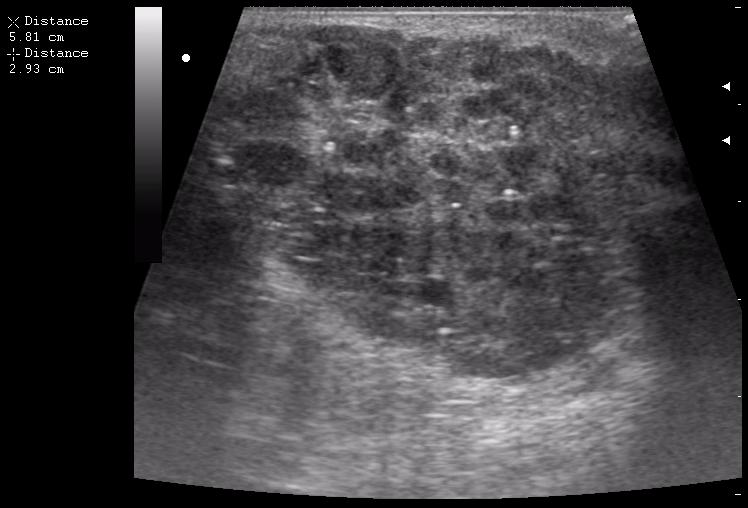

пакеты гиперплазированных лимфоузлов